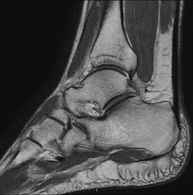

Exploració per estudiar aquesta articulació i les lesions freqüents de lligaments (esquinços), així com l'afectació d'altres estructures, com el cartílag o l'os. També és de gran utilitat per diagnosticar alteracions al tendó d'Aquil·les (tendinitis o trencaments). La durada aproximada és de 20 minuts. No utilitza radiació ionitzant. - RM de Peu